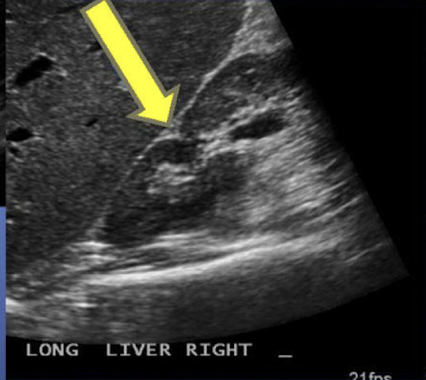

What is this image showing?

More of the liver is shown in this image so it is the ________ kidney

Right kidney is shown